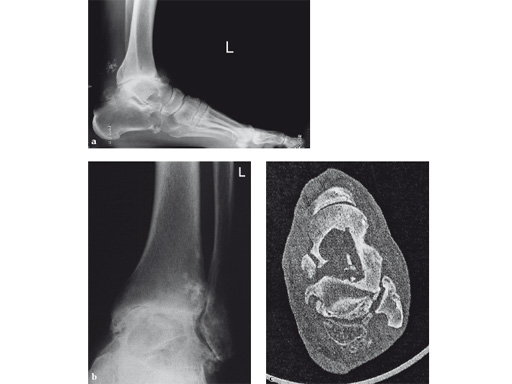

A 64-year-old man presented with severe ankle and subtalar arthritis accompanied by large cysts in the talus and calcaneus. Eighteen months after hindfoot fusion with the HAN he walked without pain.

Case provided by Stefan Rammelt, Dresden, Germany